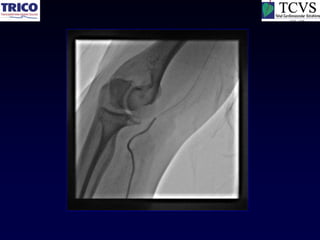

Radial Artery Spasm

Working through

Calcified Radial Artery